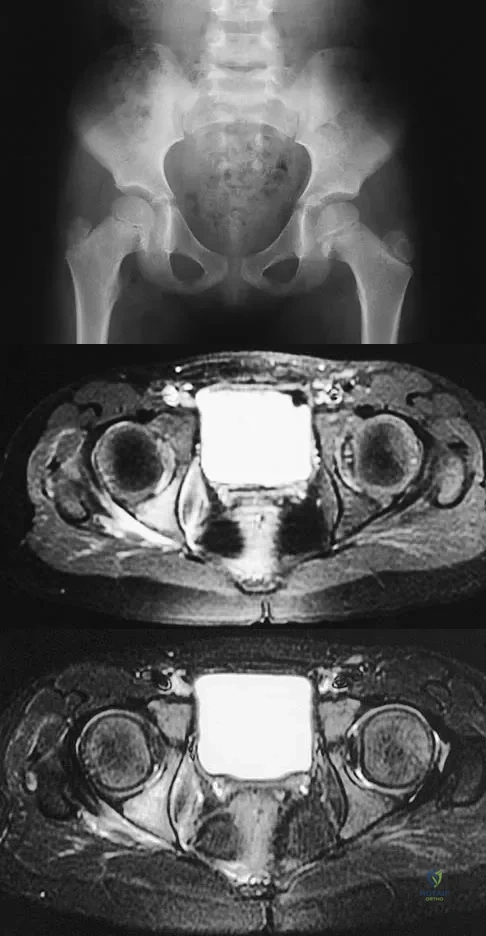

Figures 1a through 1c show the radiograph and MRI scans of a 16-year-old patient who has a painful hip. Examination reveals a significant limp, limited abduction and internal rotation, and severe pain with internal rotation and adduction. A biopsy specimen is shown in Figure 1d. What is the deposited pigment observed in this condition?

Explanation